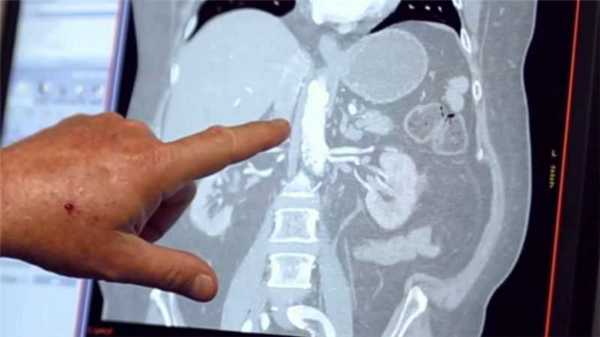

Radiology department of the Rijnland Hospital Leiderdorp and the University Medical Centre Groningen, the Netherlands.КТ-ангиография сосудов брюшной полости

![КТ-ангиография сосудов брюшной полости]()

КТ-ангиография сосудов брюшной полости считается одним из наиболее современных методов определения состояния здоровья сосудистой системы в указанной области. Его главным отличием выступает привлечение специального контрастного вещества.

Обычное ультразвуковое исследование не способно предоставить развернутую картину по структуре и общему состоянию сосудов в брюшной области, что способствовало разработке и внедрению технологии ангиографии. Вместе с контрастом получается визуализировать абсолютно все участки сосудистого русла. На основе полученной визуализации доктор сможет определить не только строение больших и мелких сосудов, но также выявить возможные аномалии в близлежащих органах.

Детализированная картина помогает обнаружить даже малейшие просветы, либо выявить внутренние образования, будь то онкологические опухоли или обычные тромбы. Причем изображение настолько подробно, что опытный рентгенолог способен на его основе распознать только-только зарождающиеся заболевания. Особенно актуален поиск недугов на начальной стадии развития для онкологических заболеваний.

Основные показания для назначения

На фоне многочисленных аналогичных вариантов методика компьютерной томографии, приспособленная для изучения сосудов, дает гораздо меньший процент ложных сведений. Это позволяет ей фиксировать даже крохотные аневризмы, которые за короткий промежуток времени быстро увеличиваются. Свойственно подобное преобразование селезеночной артерии.